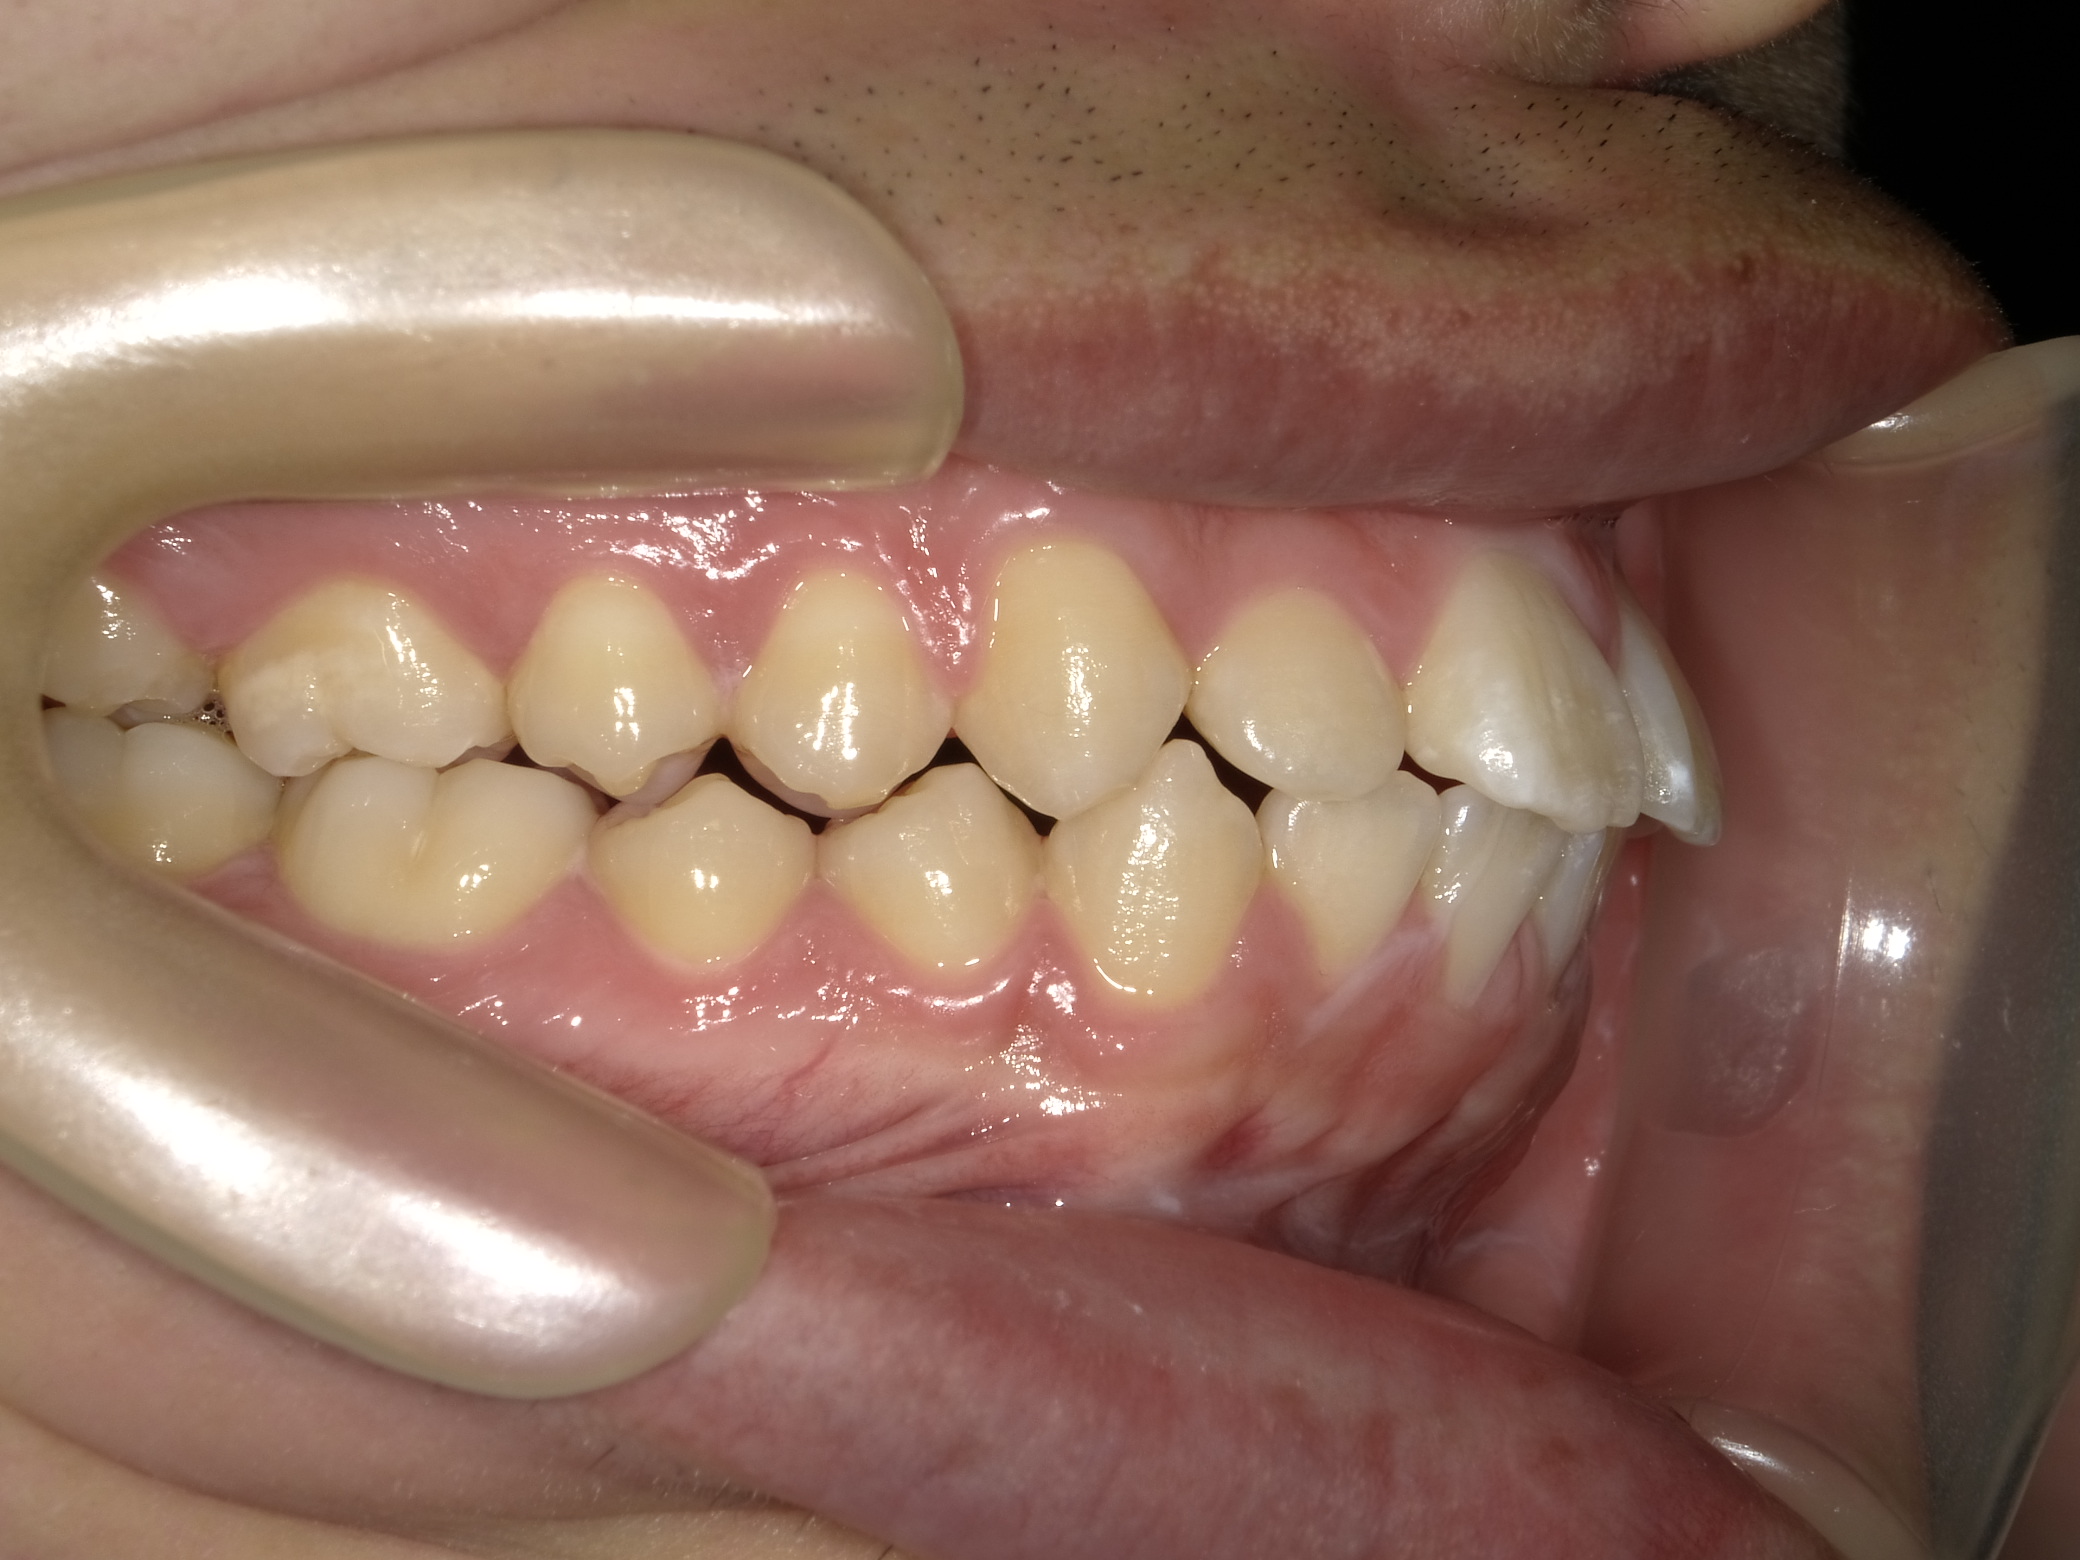

| 症例分類 | 上下顎前突 |

|---|---|

| 主訴 | 前歯が出ていて、口が閉じにくい |

| 年齢 | 20歳0ヶ月 |

| 性別 | 男性 |

| 抜歯部位 | 上下顎両側第一小臼歯 |

| 使用装置 | 歯の表側からのマルチブラケットによる矯正装置 |

| 治療期間 | 2年10ヶ月 |

| 保定装置 | 取り外し式保定装置 |

| 費用 | 相談料0円、検査料55,000円 動的矯正治療費935,000円 調整料6,600円×28回分 保定装置料0円 |

| リスク・注意点 | 上下の個々の歯の大きさに対して上下の顎が小さく歯が並ぶスペースが不足したために上下の前歯が前方に傾斜して、上下顎前突が生じています。これらを改善するために、上下顎両側第一小臼歯を抜歯して、このスペースを用いて歯を排列しました。歯の動き方には個人差があり、予想された治療期間が延長する可能性があります。 治療中は矯正歯科装置が歯の表面に付いており、歯が磨きにくくなるため、むし歯や歯周病が生じるリスクが高まります。ハミガキを適切に行ってお口の中を常に清潔に保ち、さらに、かかりつけ歯科医に定期的に受診することが大切です。 顎間ゴムの使用状況、定期的な通院など、矯正歯科治療には患者さんの協力が必要であり、それらが治療結果や治療期間に影響します。 治療の経過によっては当初予定していた治療計画を変更する可能性があります。 歯を動かすことにより歯根が吸収することがあります。 保定装置の装着時間が十分確保できない場合、歯並びや、咬み合せの「後戻り」が生じる可能性があります。 |